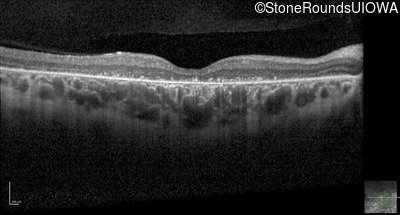

Optical Coherence Tomography - Right - 10/140 sc

Exemplar / OCT Stack